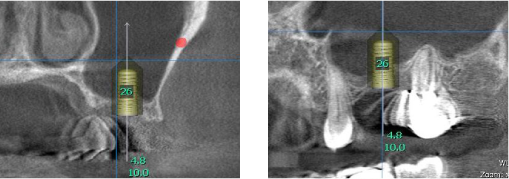

上顎洞までの距離はわずか2mmしかありません。 これではインプラントは出来ません。

下図のように上顎洞に骨になる材用を封入しました。